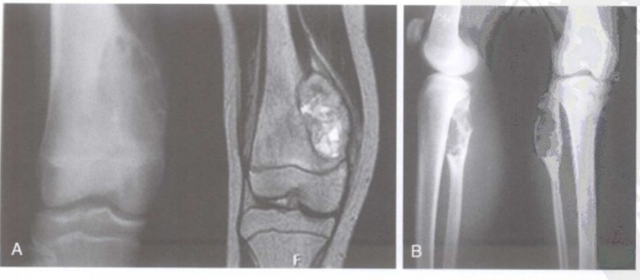

骨伤科脊柱·肿瘤二组杨林主治医师接诊后,立即为李先生完善了胸部、椎体及肋骨CT检查,检查结果提示:胸8椎体肿瘤及右侧第8肋骨肿瘤。

随后,骨伤科脊柱·肿瘤二组联合胸心外科共同为李先生制定手术治疗方案,一切准备就绪后,骨伤科脊柱·肿瘤二组手术团队顺利为其实施了“经前路胸8椎体肿瘤及肋骨肿瘤根治性切除+人工椎体植入内固定+胸腔闭式引流术”,术后病理报告骨囊肿,目前已康复出院。